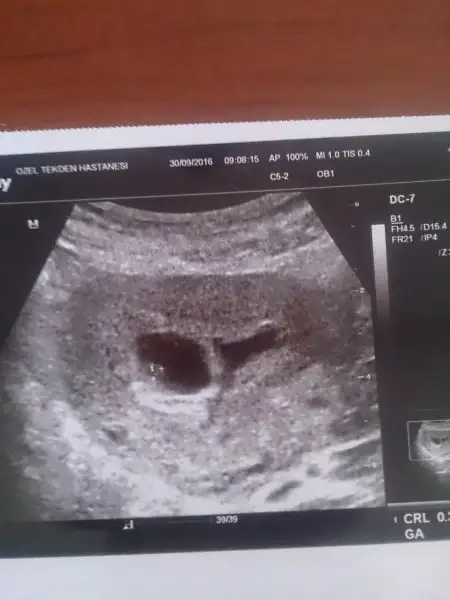

Hoşgeldin hayırlı olsun inşallah bebişin..Merhabalar guzel anneler ve anne adayları. Bende 3 gün önce öğrendim hamile olduğumu. Gerçi hala inanamıyorum. Aslında predictor testiyle yumurta takibi yapmıştık bu ay ama olmasıni beklemiyordum. Regli gecinkince ve kokulara karşı anormal bir durum gerçekleşince dur bir bakayım dedim. Meger hamileymisim. Sajirim mayıs ayının en küçüğü biziz ikinci bebeğimi bekliyorum ve antalyada yaşıyorum. İlk bebeğim kız ve şuan 2 yaşında. Bu hamileliğimde doktora gitmeyi açıkçası düşünmüyorum. Ultrasonun zararlı olmadığı soylense de kesinlik mevcut değil. Zararlı ışınlarla maruz bırakmak istemiyorum yavrumu. Her hangi bir şey olursa zaten anlayaağımıza ümit ediyorum. Cinsiyeti de doğum da öğrenecektik ama sanırım o kadar idareli olamayacağız. İlk bebeğimi sezeryan ile dünyaya getirmemek rağmen bu bebeğimi normal doğumla dünyaya getirmek istiyorum ki öyle de olacak. Herkese merhaba diyorum yeniden aranıza hoş geldim